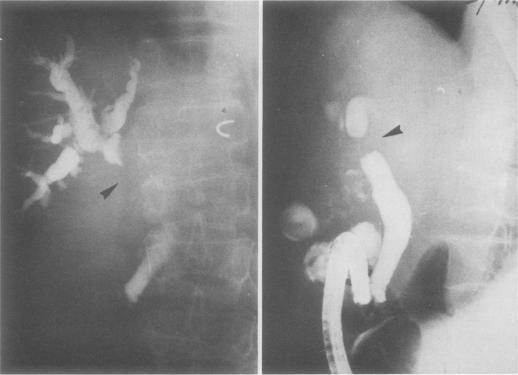

Three patients with mucoepidermoid carcinoma of the bile duct are described. In two patients the tumor arose from the common hepatic duct. Mucoepidermoid carcinoma of the extrahepatic bile duct has not been previously reported. The clinical features and pathologic behavior of this rare type of tumor are similar to the usual biliary adenocarcinoma. The coexistence of Clonorchis sinensis infestation and primary pyogenic cholangitis raises the possibility of an etiologic association.

本文描述了3例胆管黏液表皮样癌患者。其中2例肿瘤起源于肝总管。肝外胆管黏液表皮样癌此前未见报道。这种罕见类型肿瘤的临床特征和病理行为与常见的胆管腺癌相似。华支睾吸虫感染与原发性化脓性胆管炎并存增加了病因学关联的可能性。